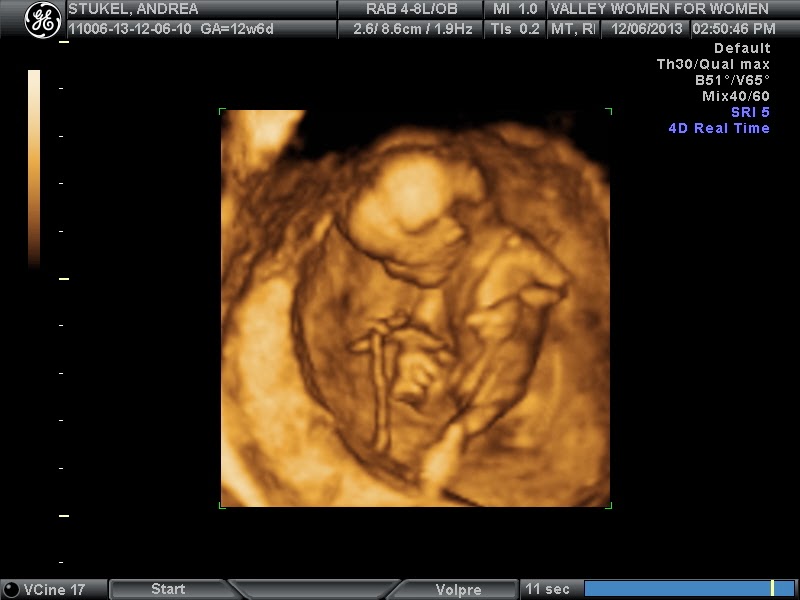

size of baby: a lime, or in other more technical terms 6.75 cm at 12 wk 6 days. also it looks like it is in the 62.5% percentile

best moment of the week: getting to see our little one on ultrasound, moving and kicking, and looking like an actual baby

check out those long legs, taking after dad on that trait for sure and 5 little fingers as well....

4D image was pretty neat, it was mostly awesome to watch her move, she was a little shy here

and my favorite image, grabbing her little foot, i think she is practicing her dance moves ;)